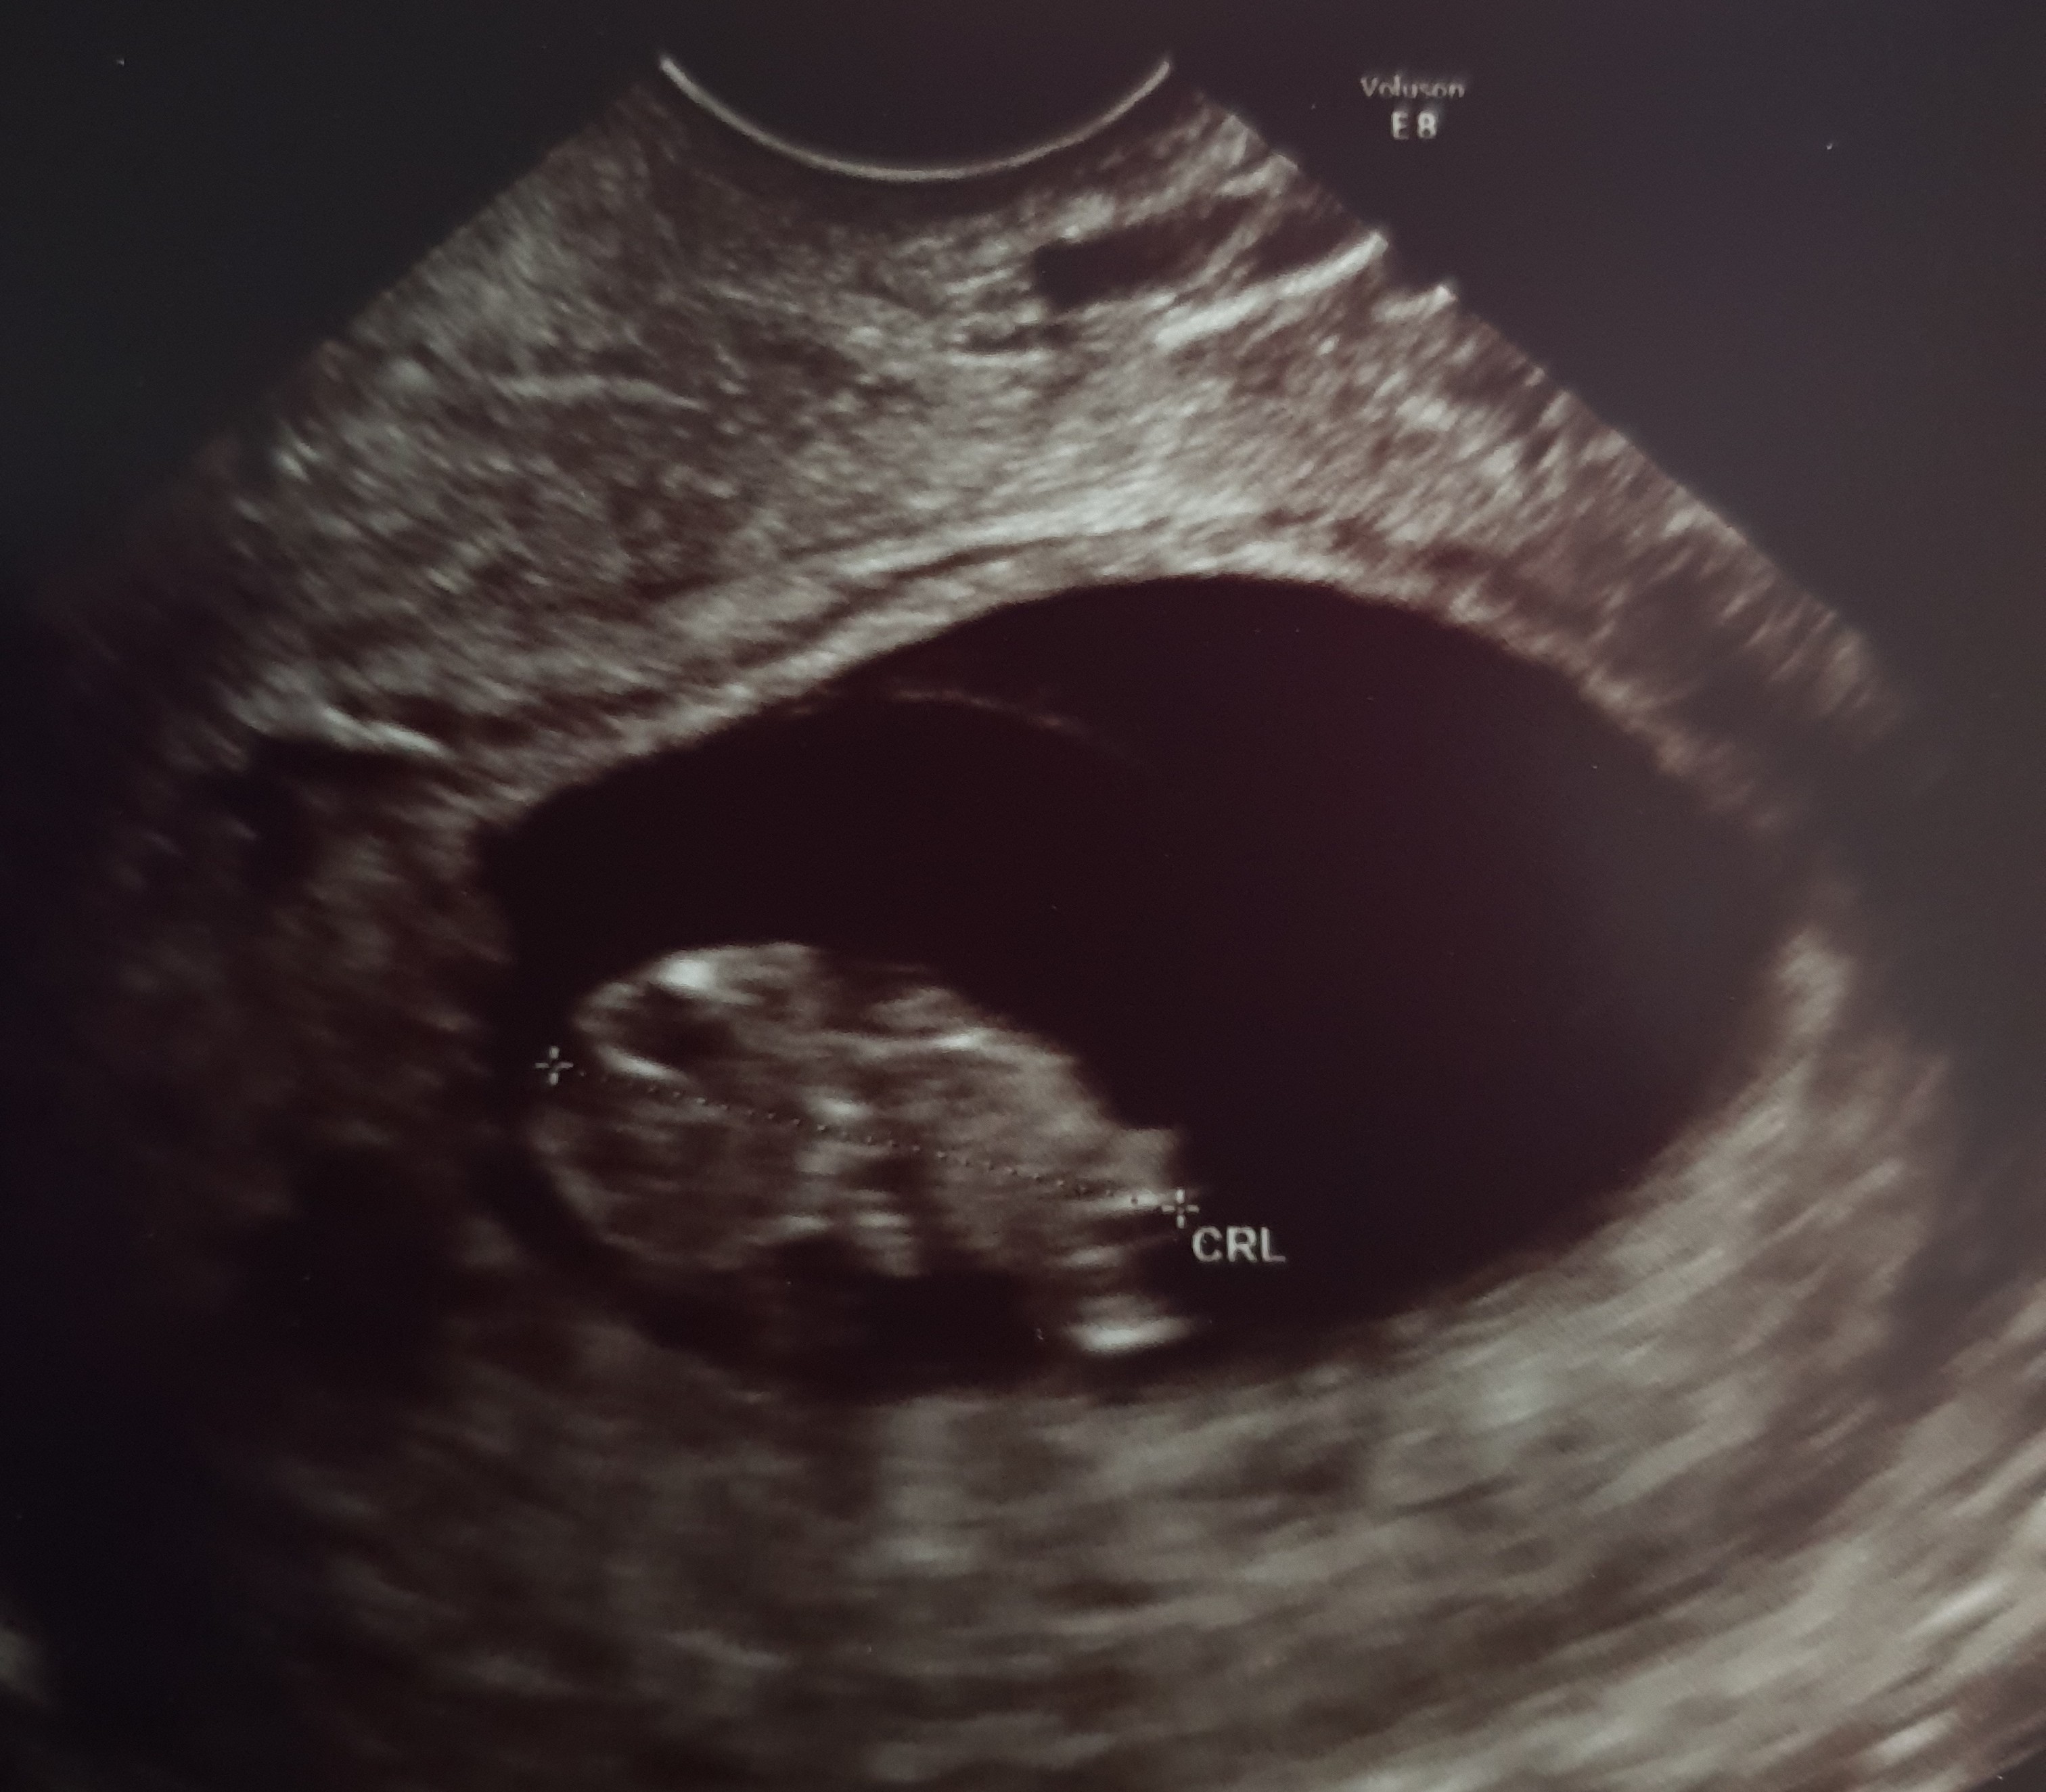

Hej, ja właśnie po wizycie, ubłagałam lekarza, żeby zrobił mi dziś dodatkowe usg po tych skokach cukru, bo się nerwów najadłam. Mamy 9 +2, maluszek ma już 2,5 cm, serducho bije pięknie.. Jednym słowem wszystko ok [emoji108]. Dostałam insulinę dlugodziałajacą na noc i szykuje się już do sylwestrowej nocki (balu nie będzie, ale jakoś trzeba uczcić te dobre wieść). Szczęśliwego Nowego Roku dziewczyny :)